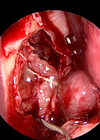

Endoscopic excision of cholesteatoma

In this article Vikranth Visvanathan describes an exciting development on the use of endoscopic technology in complex otological practice. Transcanal endoscopic ear surgery (TEES) is rapidly evolving as a recognised method of addressing middle ear and mastoid pathology. Since its...